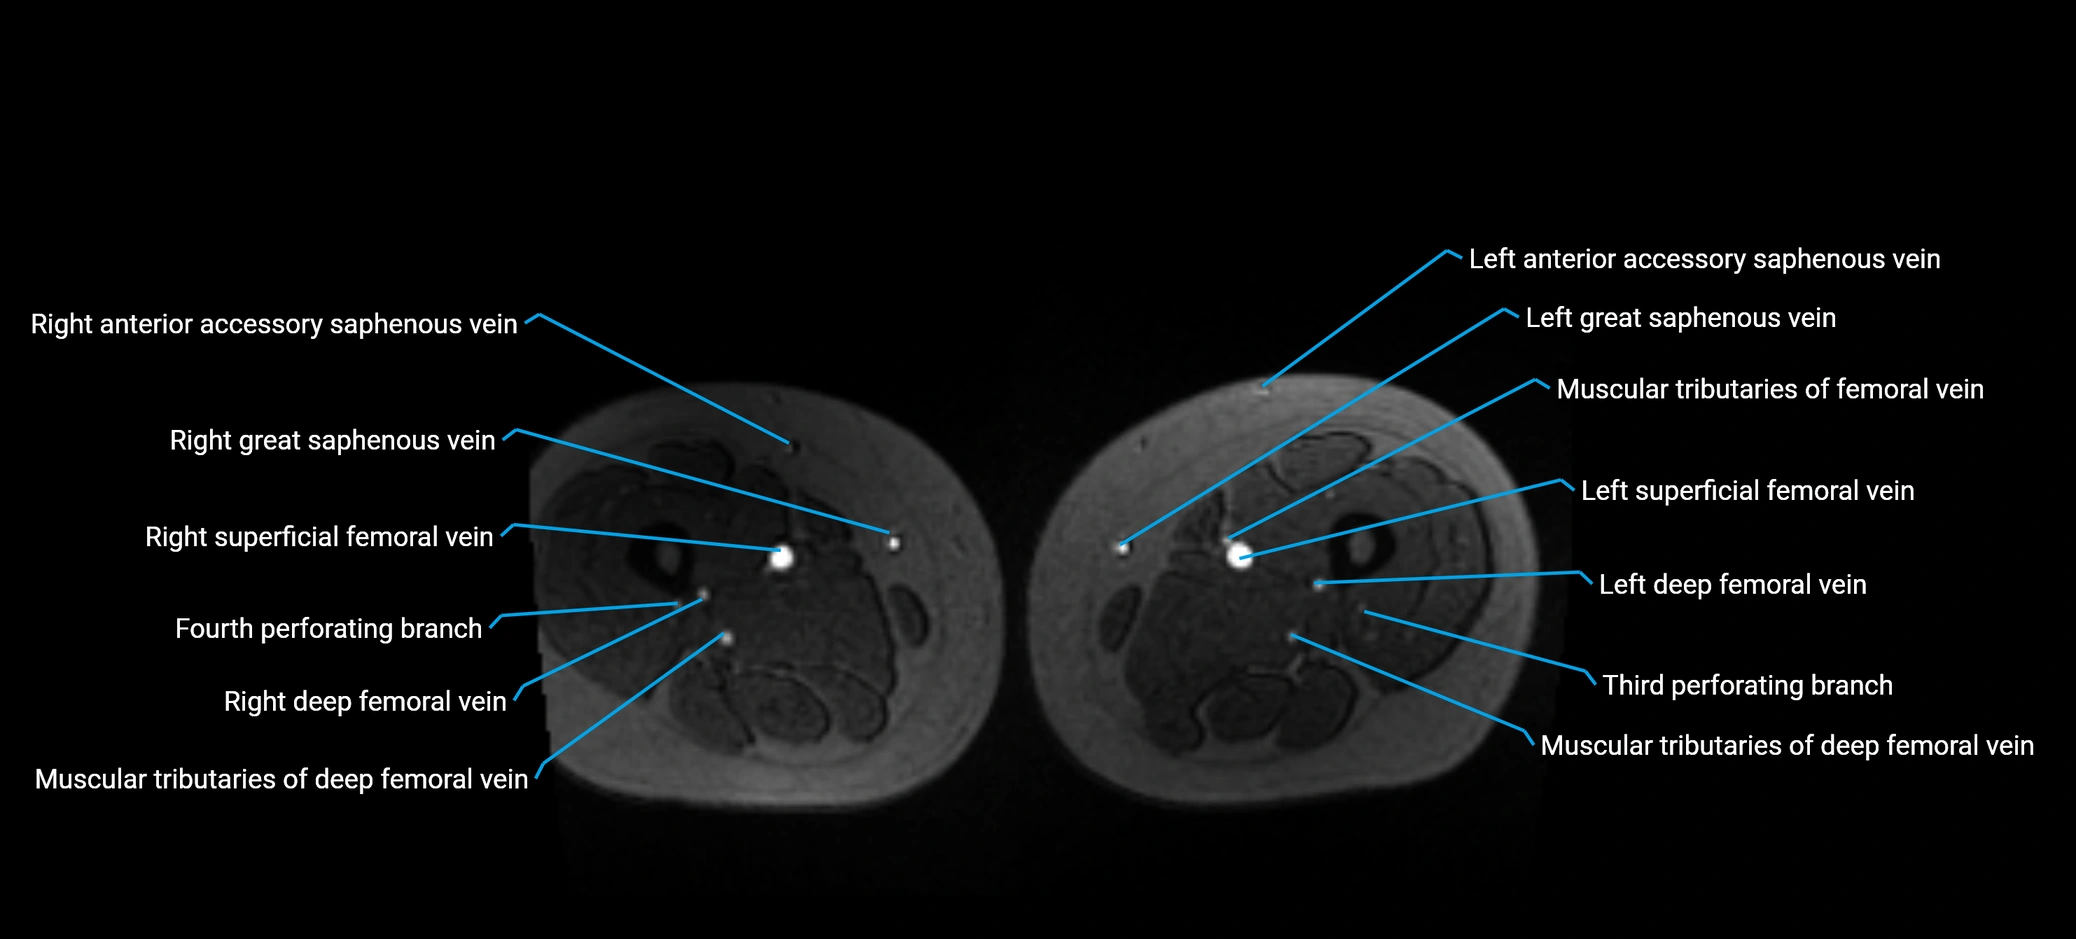

MRI image

image